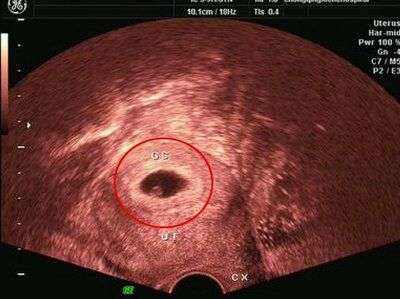

孕囊其實只有在懷孕早期可以看得見,當孕媽咪還不知道自己已經懷孕,只知道該來的月經還沒來的時候,如果一旦確定懷孕,那么就要從上次停止月經的時間計算預產期。而從上次停止月經的時間計算,向后數35天,那么孕囊基本上就能在B超里顯示出來了。而這時已經是懷孕第五周了,這個時候孕囊的直徑大小約為2cm。

隨著胎兒的不斷增長,孕囊也會不斷的擴大的,到了孕8周,也就是懷孕60天左右的時間時,孕囊的直徑可以增加到5cm。此時觀察到的孕囊,其位于子宮的宮底、前壁、后壁、上部、中部等位置,清晰可見,而且呈規則的橢圓形或者圓形。但是也有一種可能,孕囊位于子宮的下部,而且形狀不規則,且通過B超發現有些模糊,而此時孕婦主訴有腹痛或者見紅的現象,那么這位孕婦很有可能要流產了。(揭秘羊水指數標準!教您如何進行測量羊水量?)

細心的孕媽咪可能會發現,在孕早期的B超單上,都會顯示孕囊的大小,尺寸大小直要比寶寶的體長大出一倍左右,基本上是沒有問題的。